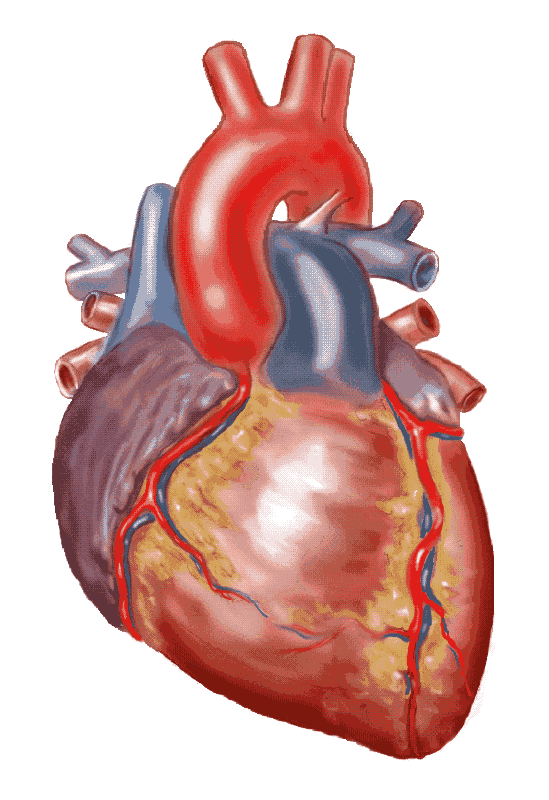

3d anatomy human heart  Show me a diagram of the human heart? Here are a bunch! - Interactive Biology, with Leslie Samuel

3d human heart anatomy model  //thebrainstormlab.com/banners/ami_banner.jpgThis is a medical | Heart anatomy drawing, Human

//thebrainstormlab.com/banners/ami_banner.jpgThis is a medical | Heart anatomy drawing, Human  Human Heart Section 3D model | CGTrader

Heart Anatomy Human Heart Images Hd 3D - Dreaming Arcadia  Anatomical Heart Drawing at GetDrawings | Free download

Human Heart Anatomy 1 3D model | CGTrader  How to draw realistic human heart||3d human heart sketch

How the Human Heart Works | Safety and Health Solutions  3d human heart

Heart Anatomy Human Heart Images Hd 3D - Dreaming Arcadia  Realistic Human Heart 3D model | CGTrader

Heart Anatomy Human Heart Images Hd 3D - Dreaming Arcadia  Pin on Body Parts Drawings

Heart Diagram Human Heart Images Hd 3D - img-Badr  Real Human Heart Drawing at GetDrawings | Free download